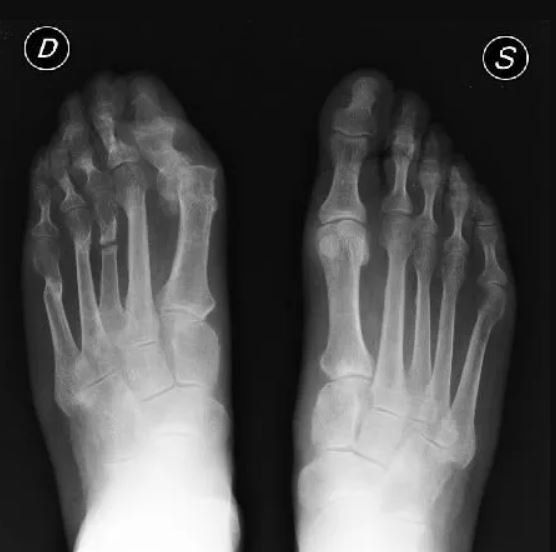

- recidiva di alluce valgo;

- metatarsalgie da trasferimento in esito correzione dell’avampiede;

In particolare per la chirurgia del piede è abbastanza frequente incontrare pazienti che lamentano dolore dopo un intervento correttivo per l'alluce valgo, visto l'elevato numero di pazienti che si sottopongono ad intervento. Il motivo più comune dell’insorgenza del dolore è la metatarsalgia da trasferimento, seguita dalla recidiva di alluce valgo e in minore misura della deformità delle altre dita.

In varie rivalutazioni delle casistiche sulle revisioni appare chiaro come i risultati chirurgici mediocri e la necessità di una revisione chirurgica, potrebbero essere prevenuti con la selezione di tecniche chirurgiche che evitino la distruzione articolare, l'accorciamento eccessivo dei singoli metatarsi e l'amputazione digitale.